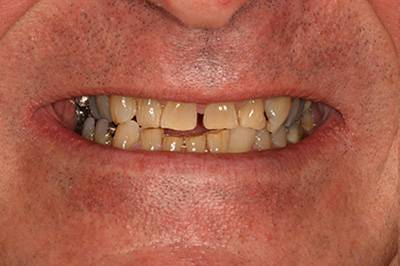

6. Eset

Nagymértékű fogkopás, erózió, csikorgatás a teljes rágóapparátust túlterhelve okoz reménytelennek tűnő helyzeteket.

Ebben az esetben implantátumok , koronák és hidak segítségével változtattunk a páciens fogainak érintkezésén. 6 hónapig ideiglenes hidakkal teszteltük a megváltoztatott harapási pozíciót. Ezután készültek el a végleges fix pótlások.